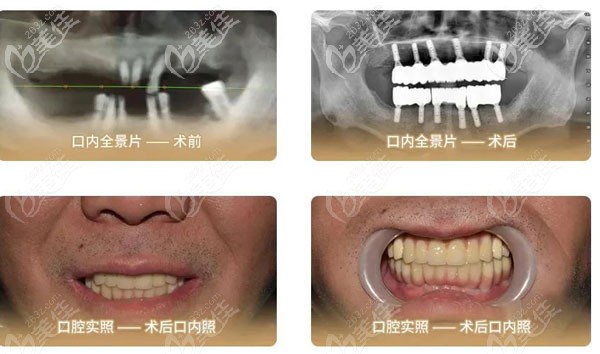

PS:“立得用·種植牙”體系,主要是針對(duì)半口/全口無牙顧客,通過植入4顆/8顆種植體來達(dá)到重建半口/全口牙齒的效 果。

不僅可以減少種植體的植入,節(jié)省費(fèi)用,還實(shí)現(xiàn)了術(shù)后即刻負(fù)重。因?yàn)橹兄Z有自己的牙冠加工廠,和技師團(tuán)隊(duì),因此當(dāng)天種牙、當(dāng)天戴牙冠,一次性搞定,不是難事。